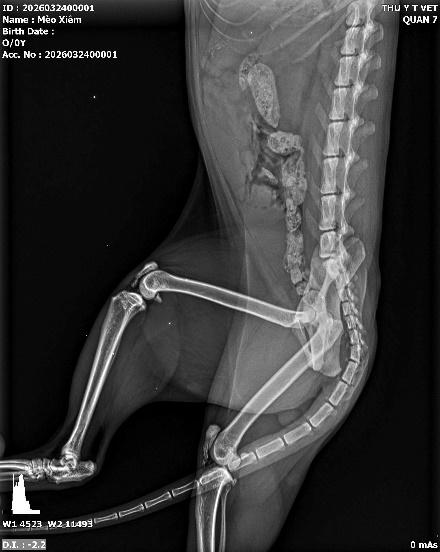

Tình trạng táo bón kinh niên dẫn đến giãn đại tràng (Megacolon) rất thường gặp ở mèo già hoặc mèo ăn quá nhiều xương nhưng ít uống nước. Trên phim X-quang, bác sĩ sẽ thấy hình ảnh đại tràng giãn lớn, chứa đầy khối phân nén chặt, khô cứng. Nếu không giải quyết kịp thời, độc tố từ phân sẽ thấm ngược vào máu gây nhiễm độc cơ thể. Chụp X-quang giúp chúng tôi đánh giá mức độ nghiêm trọng để có phương án thụt tháo hoặc phẫu thuật cắt bỏ đoạn đại tràng bị giãn.

.jpeg)

Hình ảnh: tắc phân trên bé mèo